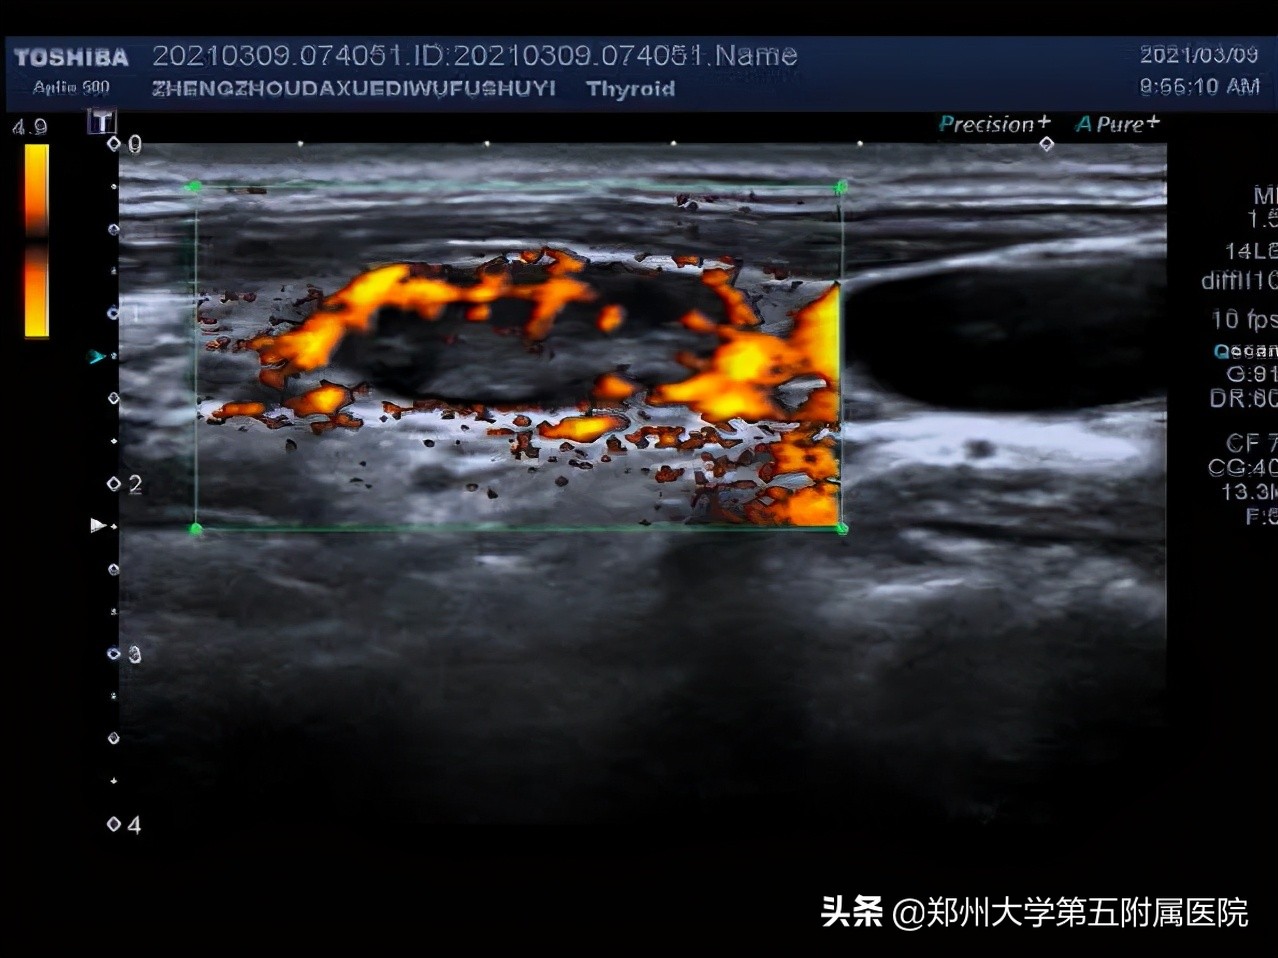

1.淋巴结皮髓质分界不清

2.淋巴结内部有液化

3.淋巴结血流为周边型,没有淋巴门。

2.不疼不痒、进行性肿大淋巴结:这些淋巴结要注意了!需要到医院做彩超检查,检查前不需要特殊准备。超声看到淋巴结内有液化、钙化、淋巴结变圆,皮髓质分界不清,淋巴结相互融合、淋巴结血流为周边型、淋巴门消失等就可能是淋巴瘤、结核、转移性肿瘤、结节病等,需告知临床医生进行进一步检查明确诊断。